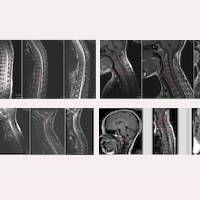

Positiver postoperativer Verlauf einer pädiatrischen Patientin mit idiopathischer Skoliose, vier Jahre nach Anwendung des Filum System® – Fall 14236 Mehr lesen » 09 Januar, 2026